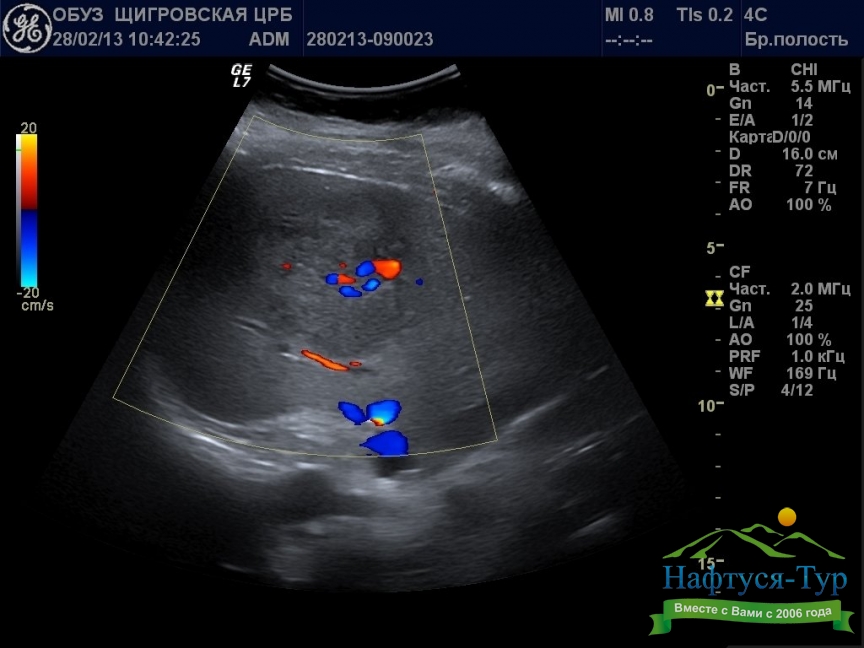

Ультразвуковое исследование (УЗИ, сонография) – неинвазивная диагностическая процедура, основанная на использовании акустических волн ультразвукового (выше порога слышимости для человека) диапазона. Используемая в санаториях техника для проведения УЗИ состоит из генератора и датчика. Генерируемые звуковые волны проникают в глубину тканей человека, при этом различные по типу ткани и инородные образования в разной степени отражают ультразвук. Отраженные волны улавливаются датчиком аппарата, накопленная информация обрабатывается компьютером, что позволяет сформировать изображение исследуемого органа.Отметим, что многие санатории имеют самые современные модели аппаратов для проведения УЗИ, в частности, позволяющие получать трехмерные и даже 4D (в динамике) изображения. Наиболее часто данный вид исследований назначают при диагностике мочекаменной и желчнокаменной болезни, заболеваниях почек, гипертонии, стенокардии.